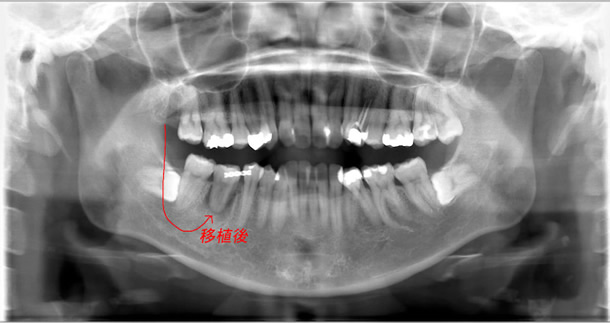

右下第一大臼歯は根の1/4付近まで虫歯に侵され、その影響で根分岐部病変も併発しており保存不可能な状態。

通常は抜歯してインプラントにするかあるいは前後の歯を削ってブリッジにするしかないが、右上奥に使われていない親知らずが存在し、移植の説明をおこなった。

患者様の同意が得られたため、自家歯牙移植を試みることになった。